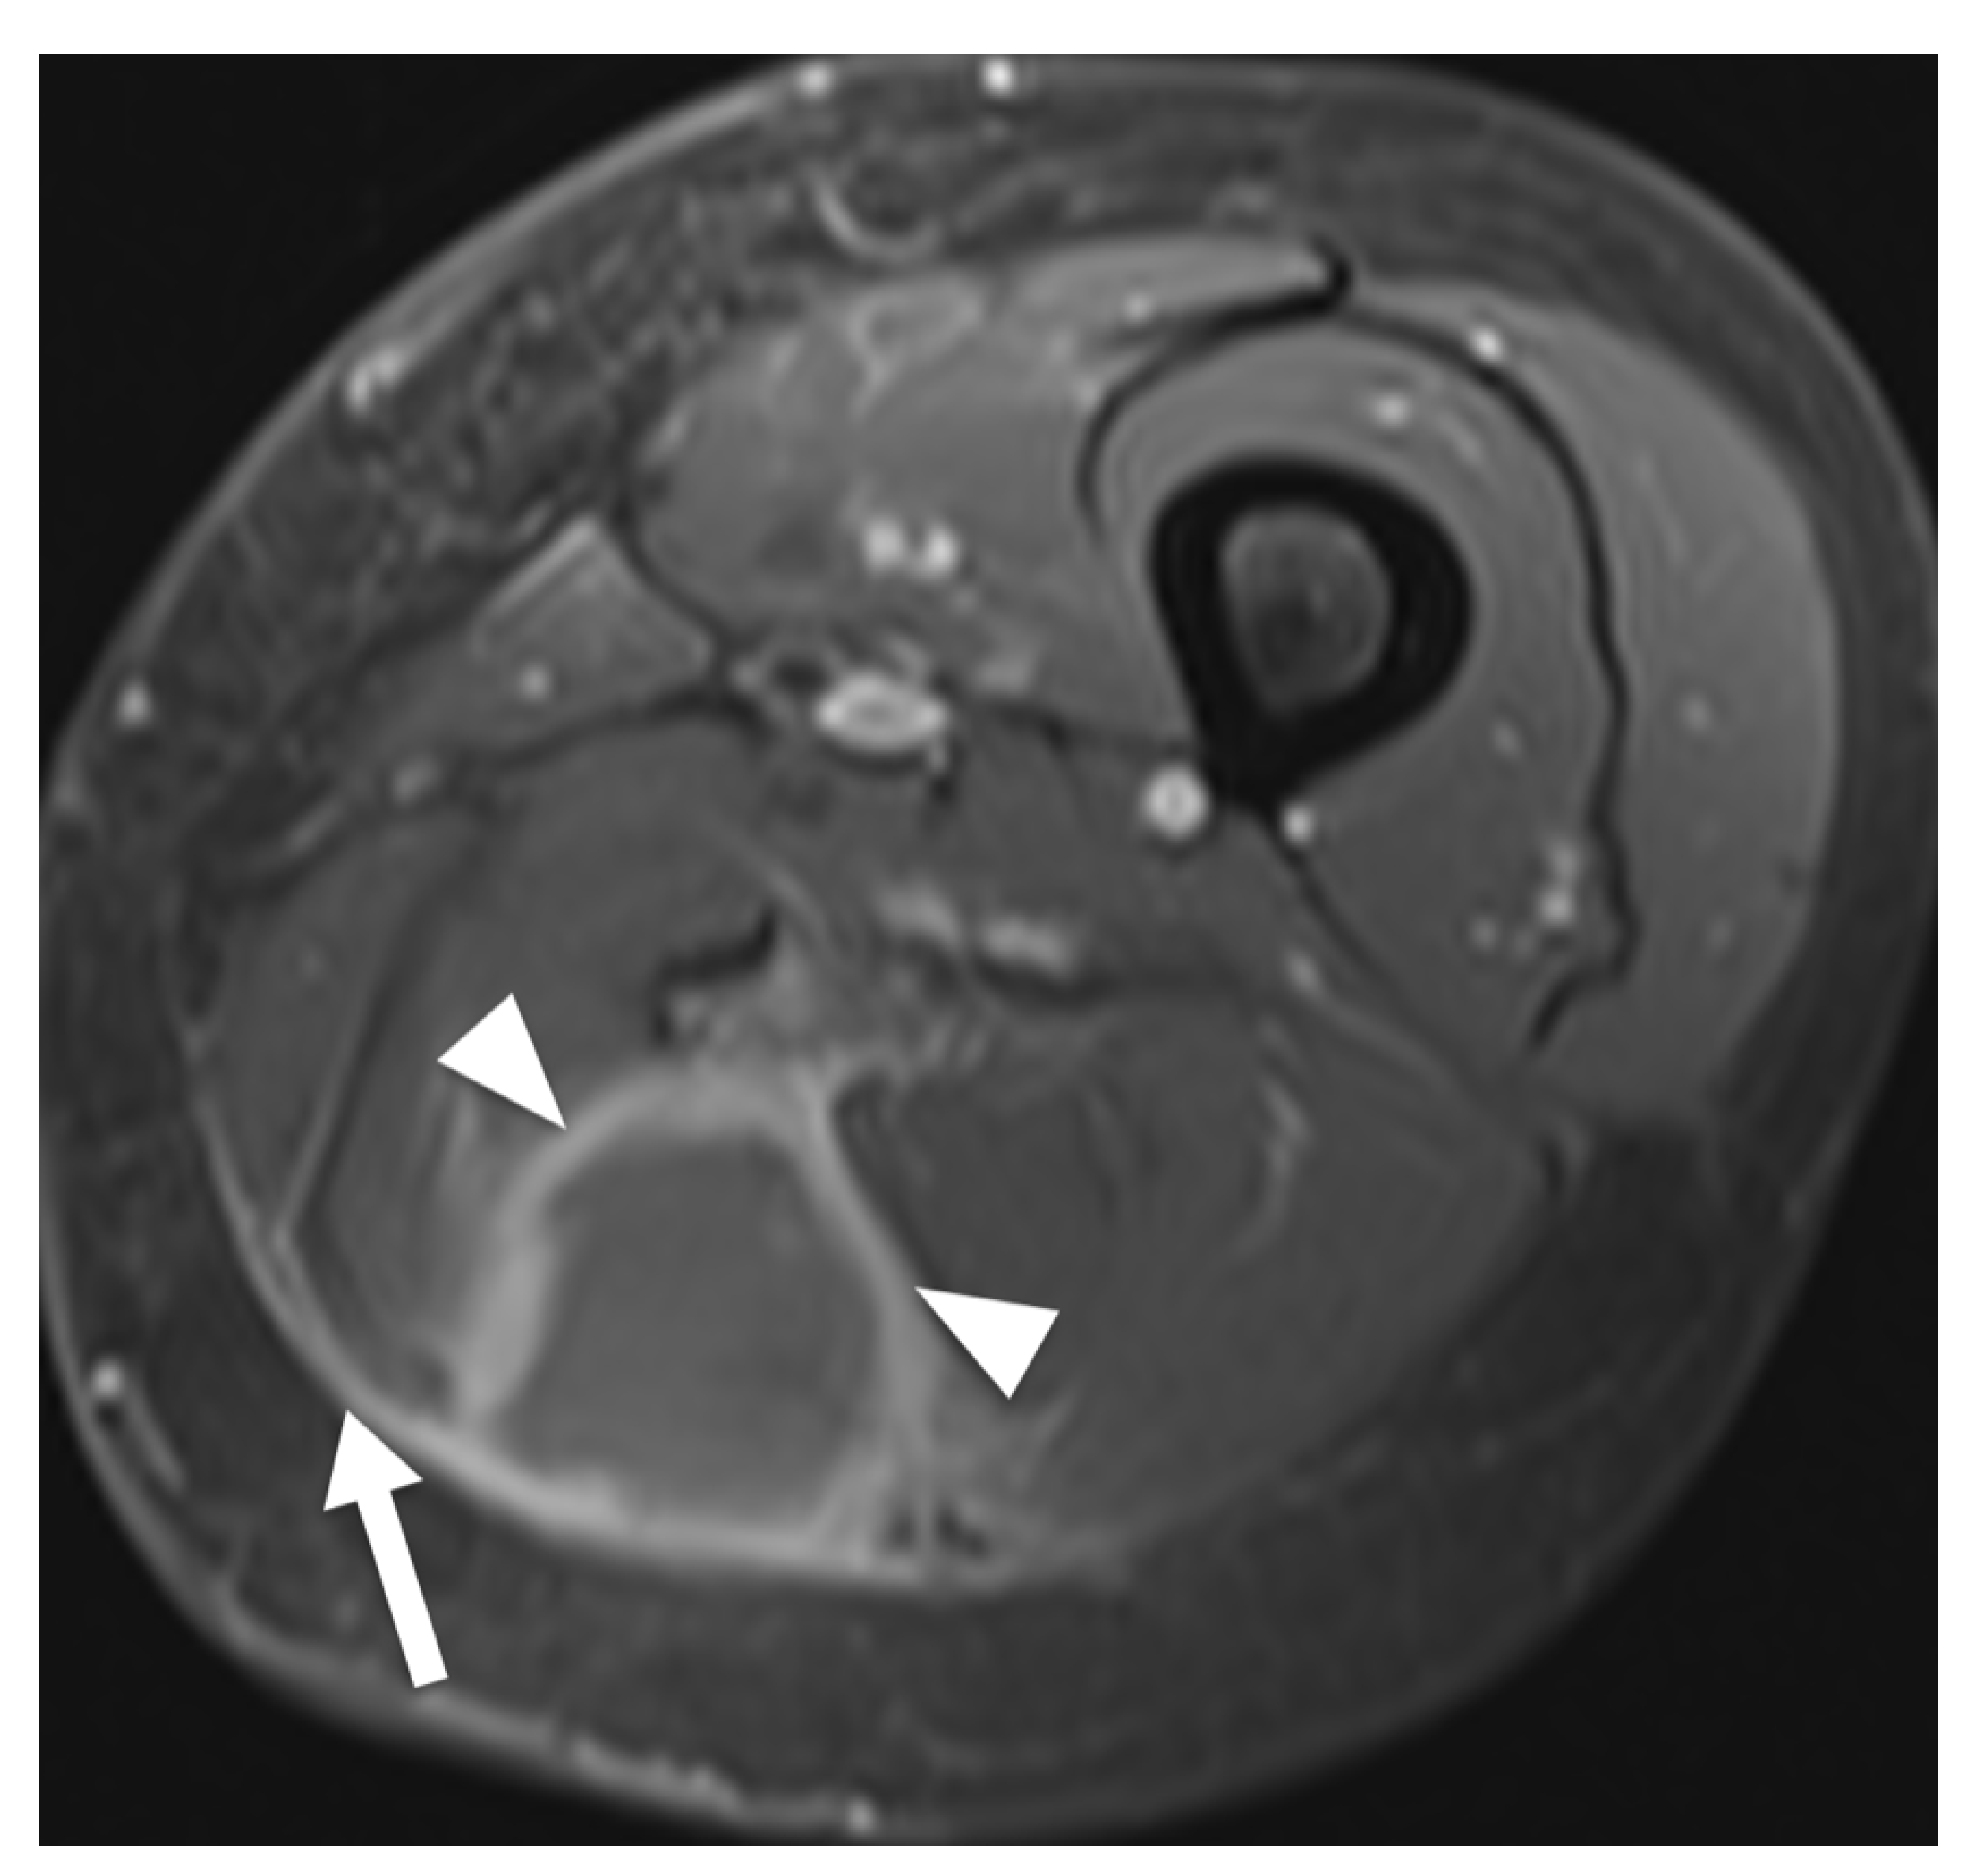

Figure 4.

MRI of a 67-year-old man presenting with a predominantly subcutaneous manifestation of non-Hodgkin lymphoma in the right axilla. (A). Transversal contrast enhanced fat-saturated T1-weighted image shows a lobulated tumor (arrow) with inhomogeneous enhancement pattern which infiltrates into the pectoralis major and minor muscles and skin (arrowheads). Moreover, an accompanying lipoma can be noted (asterisk). (B). Coronal T1-weighted image shows associated lymphadenopathy (arrowheads).

The aim of this systematic review was to identify characteristic clinical and MRI features of appendicular soft tissue lymphoma as currently described in the literature. Diffuse large B-cell lymphoma was the most commonly reported histological subtype and is also the most common type of lymphoma [36]. Clinically, ASTL presents with swelling or enlargement of muscle, which may be explained by edema due to venous or lymphatic obstruction [34,37] or actual tumor growth [33]. Moreover, regional lymphadenopathy, which may be confluent, can be present [17], (Figure 4). Signal intensity in T1W sequences consistently showed iso- to slightly hyperintense signal intensity compared to skeletal muscle. T2W sequences comparing signal intensity to skeletal muscle frequently showed hyperintense signal intensity whereas reports of signal intensity compared to fat were widely inconsistent, describing hyperintense [34] and intermediate [30] but mostly hypointense signal intensity [11,18]. The results of Lee et al. might be explained by the use of spin echo sequences, which today are widely replaced by fast spin echo (FSE) sequences and result in lower signal intensity of fat than current FSE sequences [18,32].

In T2W fat-suppressed images, signal intensity was widely inconsistent. Therefore, we conclude that iso- to slightly hyperintense signal intensity in T1W sequences and hyperintense signal intensity in T2W, STIR and PDW images compared to muscle seem to be characteristic for ASTL. Homogenous contrast enhancement was reported more frequently than heterogenous enhancement and appears to be more characteristic. A previous study described enhancement of deep and superficial fascia, these findings might be related to the tendency of infiltrative, multicompartmental growth pattern of ASTL [30]. Margin descriptions of ASTL were heterogenous, ranging from poorly to well-defined. These findings are consistent with Gao et al. as ASTL margins in MR imaging appear to be nonspecific [16]. This heterogeneity might be attributed to differences in subjective MRI interpretation between studies. Multicompartmental involvement was defined as affected muscles of multiple fascial muscle compartments [11,18,30,31,32,33,34] or as involvement of various tissues [19] and was described in 36 of 61 (59%) patients (Figure 4). This feature can be useful to differentiate ASTL from soft tissue sarcoma, which are generally known to respect compartmental boundaries [15,21,34]. The presence of subcutaneous stranding was a commonly reported attribute of ASTL [13,18,30,32] and seems to be common in ASTL presentations. Explanations for these findings could be lymphomatous infiltration or reactive edema [19,38]. Furthermore, long segmental involvement, also called cone like involvement, of tumor seems to be a key feature of ASTL, being present in 20 of 25 included patients (80%), and can present inter- or intramuscularly [30,31,34]. Involvement of neurovascular structures was reported in 12 of 29 (41%) cases [18,19]. Furthermore, a previous study evaluating CT appearance of soft tissue lymphoma has found encasement of vascular structures in confluent lymphadenopathy associated with soft tissue lymphoma in six out of 13 patients (46%) [20]. These findings might be due to infiltration along lymphatic vessels accompanying the neurovascular bundle [18]. Signal intensity abnormalities of bone marrow were occasionally described and may present edema or lymphomatous infiltration [14,34,39]. They usually present without destruction of cortical bone [10] and might be due to spread of tumor through intracortical channels, first described by Hicks et al. in cases of primary osseous lymphoma [9,14]. Additionally, the presence of traversing vessels seems to be characteristic for ASTL as it was present in 20 of 24 (83%) investigated patients (Figure 4). Necrosis is generally considered as being absent in soft tissue lymphoma manifestations before treatment [8,14,37,40]; however, there are rare reports of necrosis being present in MRI of soft tissue lymphoma manifestations [18,41]. Diffusion weighted imaging seems to pose a further asset in the characterization of soft tissue lymphoma. Reported low ADC values coincide with high cellularity of lymphoma [35,42] and seem to be significantly lower than in other malignancies such as soft tissue sarcoma and lymph node metastasis [35,43,44]. This finding might be related to the tendency of soft tissue sarcoma and metastasis to express a more heterogenous, less dense cellularity than soft tissue lymphoma [44]. Moreover, DWI could be of use to monitor the treatment response, as it has been shown, that ADC values in soft tissue sarcoma increase after radiotherapy [45]. None of the included studies investigated presence of B symptoms; this may be due to reports of soft tissue lymphoma often not presenting with symptoms such as fever, weight loss and excessive night sweat [20,41]. Moreover, alteration of lactate dehydrogenase levels seems to be a possible clinical parameter of ASTL [46,47], nevertheless, none of the included studies evaluated this variable.